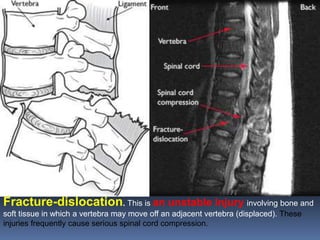

Fracture-dislocation. This is an unstable injury involving bone and

soft tissue in which a vertebra may move off an adjacent vertebra (displaced). These

injuries frequently cause serious spinal cord compression.

Fracture-dislocation. This isan unstable injury involving bone and soft tissue in which a vertebra may move off an adjacent vertebra (displaced). These injuries frequently cause serious spinal cord compression.